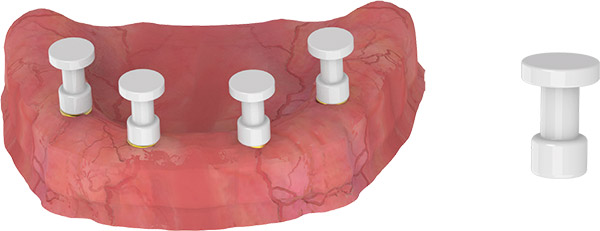

MULTI UNIT

BALL ABUTMENT

CLOSED TRAY IMPRESSION TECHNIQUE

- Use the straight and/or 17-degree Multi Base Ball Abutment in the anterior region.

- Use the 30-degree Multi Base Ball Abutment in the posterior region.

- Mount the plastic pick up transfers used for impression on 17-30 degree Multi Base Ball Abutments.

- Take the impression.

Note: The recommended insertion torque when screwing the abutment is 25 Ncm.